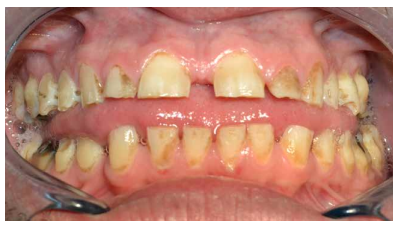

En la bibliografía se describe con detalle los defectos del esmalte que presentan los pacientes diagnosticados del síndrome de Morquio. Estos defectos son una característica aparentemente constante en la enfermedad y, por lo tanto, hace necesaria las visitas al odontólogo para su control evitándose problemas mayores. Dichos defectos consisten en un esmalte anormalmente delgado, que es áspero debido a los numerosos hoyos diminutos y a una superficie irregular. La delgadez del esmalte da como resultado una forma alterada y decoloración de los dientes que, añadido a los diastemas interdentales, provocan alteraciones en la oclusión. Aparte de estos defectos, el esmalte es histológicamente normal y tiene una dureza y radiodensidad normales. El tratamiento odontológico de los pacientes con MPS-IV requiere colaboración multidisciplinar, debido a que las manifestaciones orales de la enfermedad pueden aparecer a cualquier edad, resultando en ocasiones tedioso para el paciente y complicado para el profesional. Especial mención merecen las terapias utilizadas como tratamiento sintomático de la enfermedad, así como el manejo de la vía aérea en el caso de intervenciones bajo anestesia general o sedación para tratar ciertas patologías del territorio bucomaxilodental.

The enamel defects presented by patients diagnosed with Morquio syndrome are described in detail in the bibliography. These defects are an apparently constant feature in the disease and, therefore, make visits to the dentist necessary for their control, avoiding major problems. These defects consist of an abnormally thin enamel that is rough due to numerous tiny holes and an irregular surface. The thinness of the enamel results in an altered form and discoloration of the teeth, which added to the interdental diastemas, cause alterations in the occlusion. Apart from these defects, the enamel is histologically normal and has a normal hardness and radiodensity.

- A nivel dentario, el esmalte es uniformemente anormal, delgado, rugoso e hipoplásico. Afecta a ambas denticiones, y provocando una marcada frecuencia de fracturas dentarias, desgastes o abrasiones y caries. Existe un importante componente lingual en maloclusión, diastemas en toda la arcada y prognatismo mandibular, así como bruxismo y patología de ATM. Incisivos con forma de pala y molares cóncavos que favorece las lesiones de caries y sensibilidad dentinaria.

En la mayoría de los niños se pueden observar características dentales como cúspides puntiagudas, incisivos en forma de pala, esmalte delgado y superficies bucales con hoyos. Además, la ATM puede verse afectada con una reabsorción severa de la cabeza del cóndilo36 (Figuras 9-11).